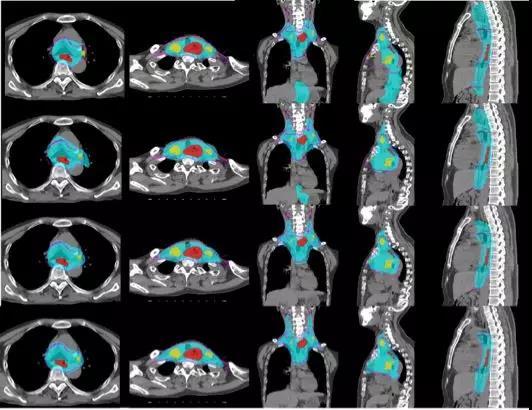

图三 食道癌放疗规划临床靶区规划的效果图